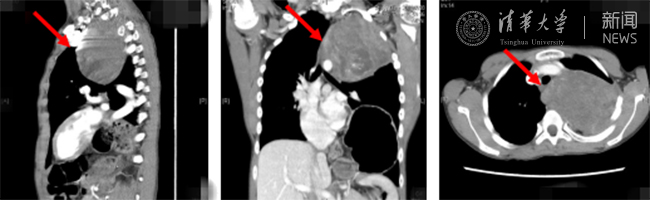

清华新闻网8月30日电(通讯员  杨峰)如图中所示,本是正常人心脏、左肺的位置,被发于神经鞘的巨大肿瘤占据,导致一位刚满12岁的男孩胸痛、咳嗽、呼吸困难。近日,北京清华长庚医院神经外科与胸外科联手,由神经外科王贵怀主任主刀,成功为男孩切除胸腔巨大神经鞘肿瘤。

患者胸腔内巨大的肿瘤。

半年前,患者经常会出现胸痛、咳嗽和呼吸困难,在当地医院检查发现左侧胸腔巨大占位,左肺及心脏明显受压。王贵怀大夫接诊,仔细查体了解病情,并反复认真阅片后,认为左侧胸腔巨大肿瘤来自于胸椎椎管内,神经鞘瘤可能性大。该肿瘤体积巨大,占据绝大部分胸腔空间,压迫左肺、纵隔大血管及膈肌。